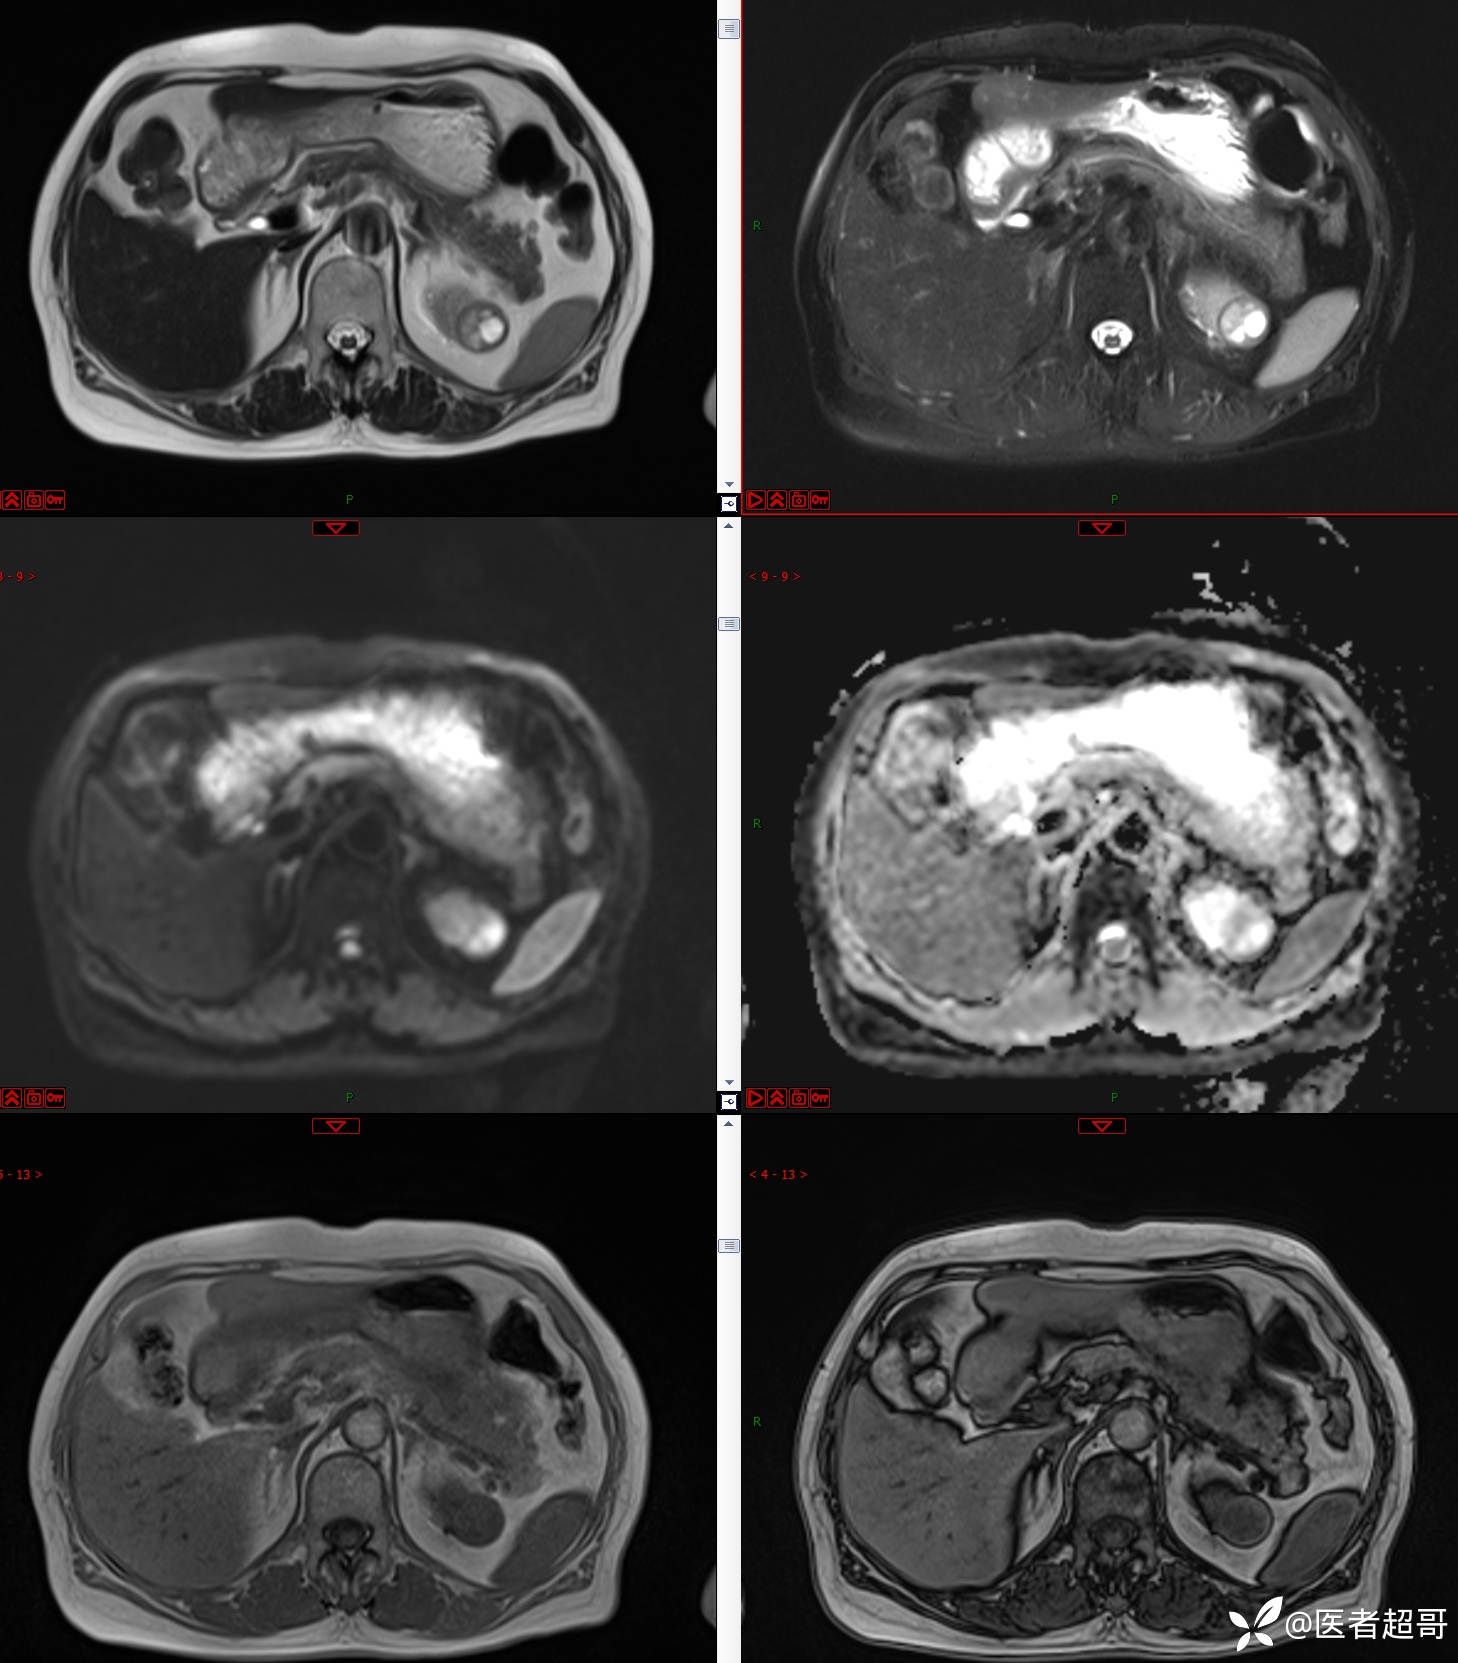

左肾占位2个月就诊,有病理,请分析!

主 诉:查体发现左肾占位2月。

现病史:患者自述2月前于镇中心卫生院行腹部超声发现:左肾实性占位。患者无尿频尿急尿痛,无发热寒战,无恶心呕吐。未行特殊治疗。现患者为求进一步诊治,就诊我院,门诊以“肾肿物”为诊断收入院,患者自发病以来,神志清,精神可,饮食可,睡眠一般,大便正常,体重未见明显改变。